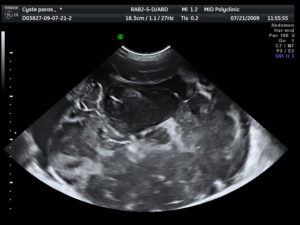

Чтобы исключить такое состояние, даже после получения положительного результата теста на беременности, стоит записаться на ультразвуковое исследование. Обычно оно проводится вагинально при помощи специального датчика.

Но так как многие женщины бояться, что такое обследование вызовет выкидыш, можно записаться на УЗИ на полный мочевой пузырь.

В таком случае врач-узист сделает процедуру абдоминально, что означает проведение процедуры на поверхности живота при помощи небольшого датчика и специального геля.